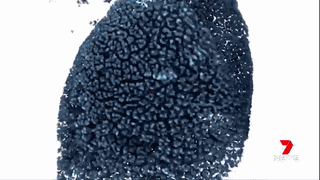

澳洲的科學(xué)家們通過運(yùn)用納米技術(shù),將“基因沉默”(gene silencing)藥物運(yùn)送至腫瘤細(xì)胞中來(lái)治療胰腺癌。

藥物已經(jīng)在擁有和人類相仿的瘢痕組織的小鼠身上進(jìn)行試驗(yàn),并獲得成功。